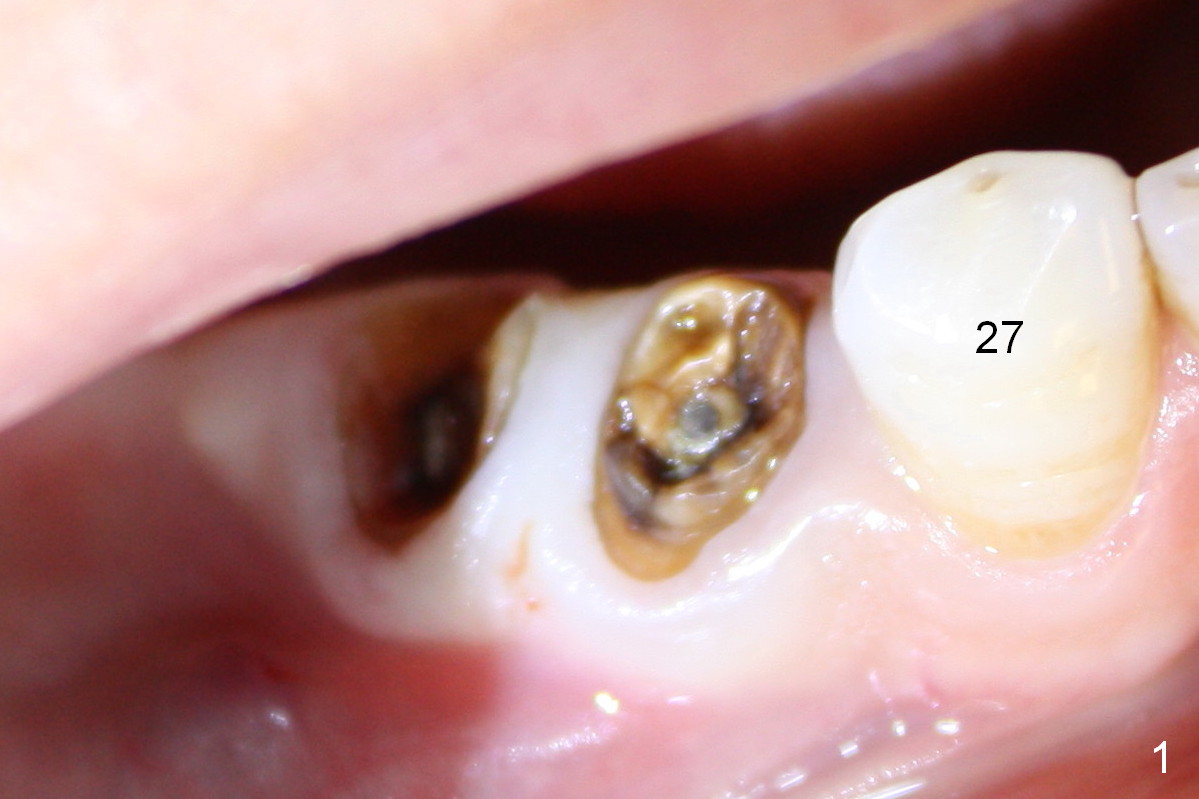

A 55-year-old lady (WJ) complains of palpation pain in the buccal vestibule over #29 implant, 5 months postop (immediately before cementation, Fig.4 *). Is the implant placed too buccally or there is buccal plate resorption after placement?

Fig.1 shows preop condition, whereas Fig.2 immediately post placement. In fact there is a space lingual to the implant of #29 (*). At that moment, the buccal margin is within normal limit (arrowheads). Ideally, the malpositioning can be corrected immediately. The implant should have been removed, repositioned and placed at the right position and trajectory. It is possible that attention was being paid to the depth of the osteotomies, because of proximity to the Mental Loop.